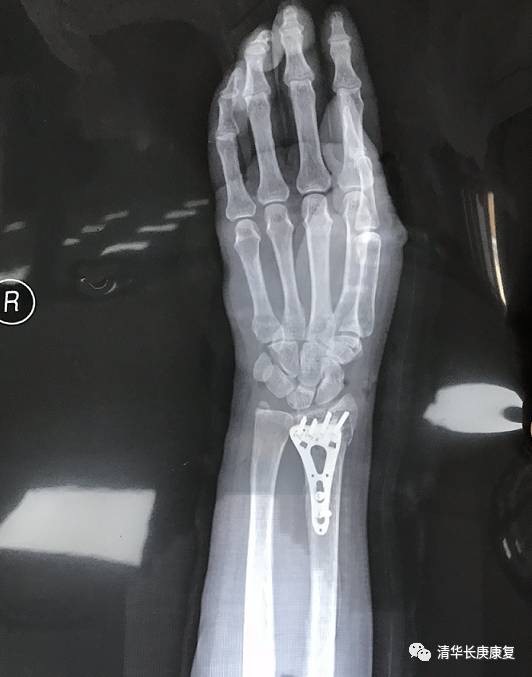

崔阿姨受伤类型属于Ⅰ类弯曲性colles骨折,骨折远端向背侧移位。因右桡骨骨折内固定手术后腕关节活动受限伴疼痛肿胀两月余,严重影响日常生活来康复科就诊。右侧腕关节X光片显示右桡尺骨骨折内固定手术后,骨折愈合良好。这与我们之前所推荐的治疗方式基本一致,崔阿姨接受了良好的外科治疗并且骨骼恢复良好,但早期并未进行正规康复训练,那么功能的延迟回复与肿胀疼痛就需要康复的介入进行处理。